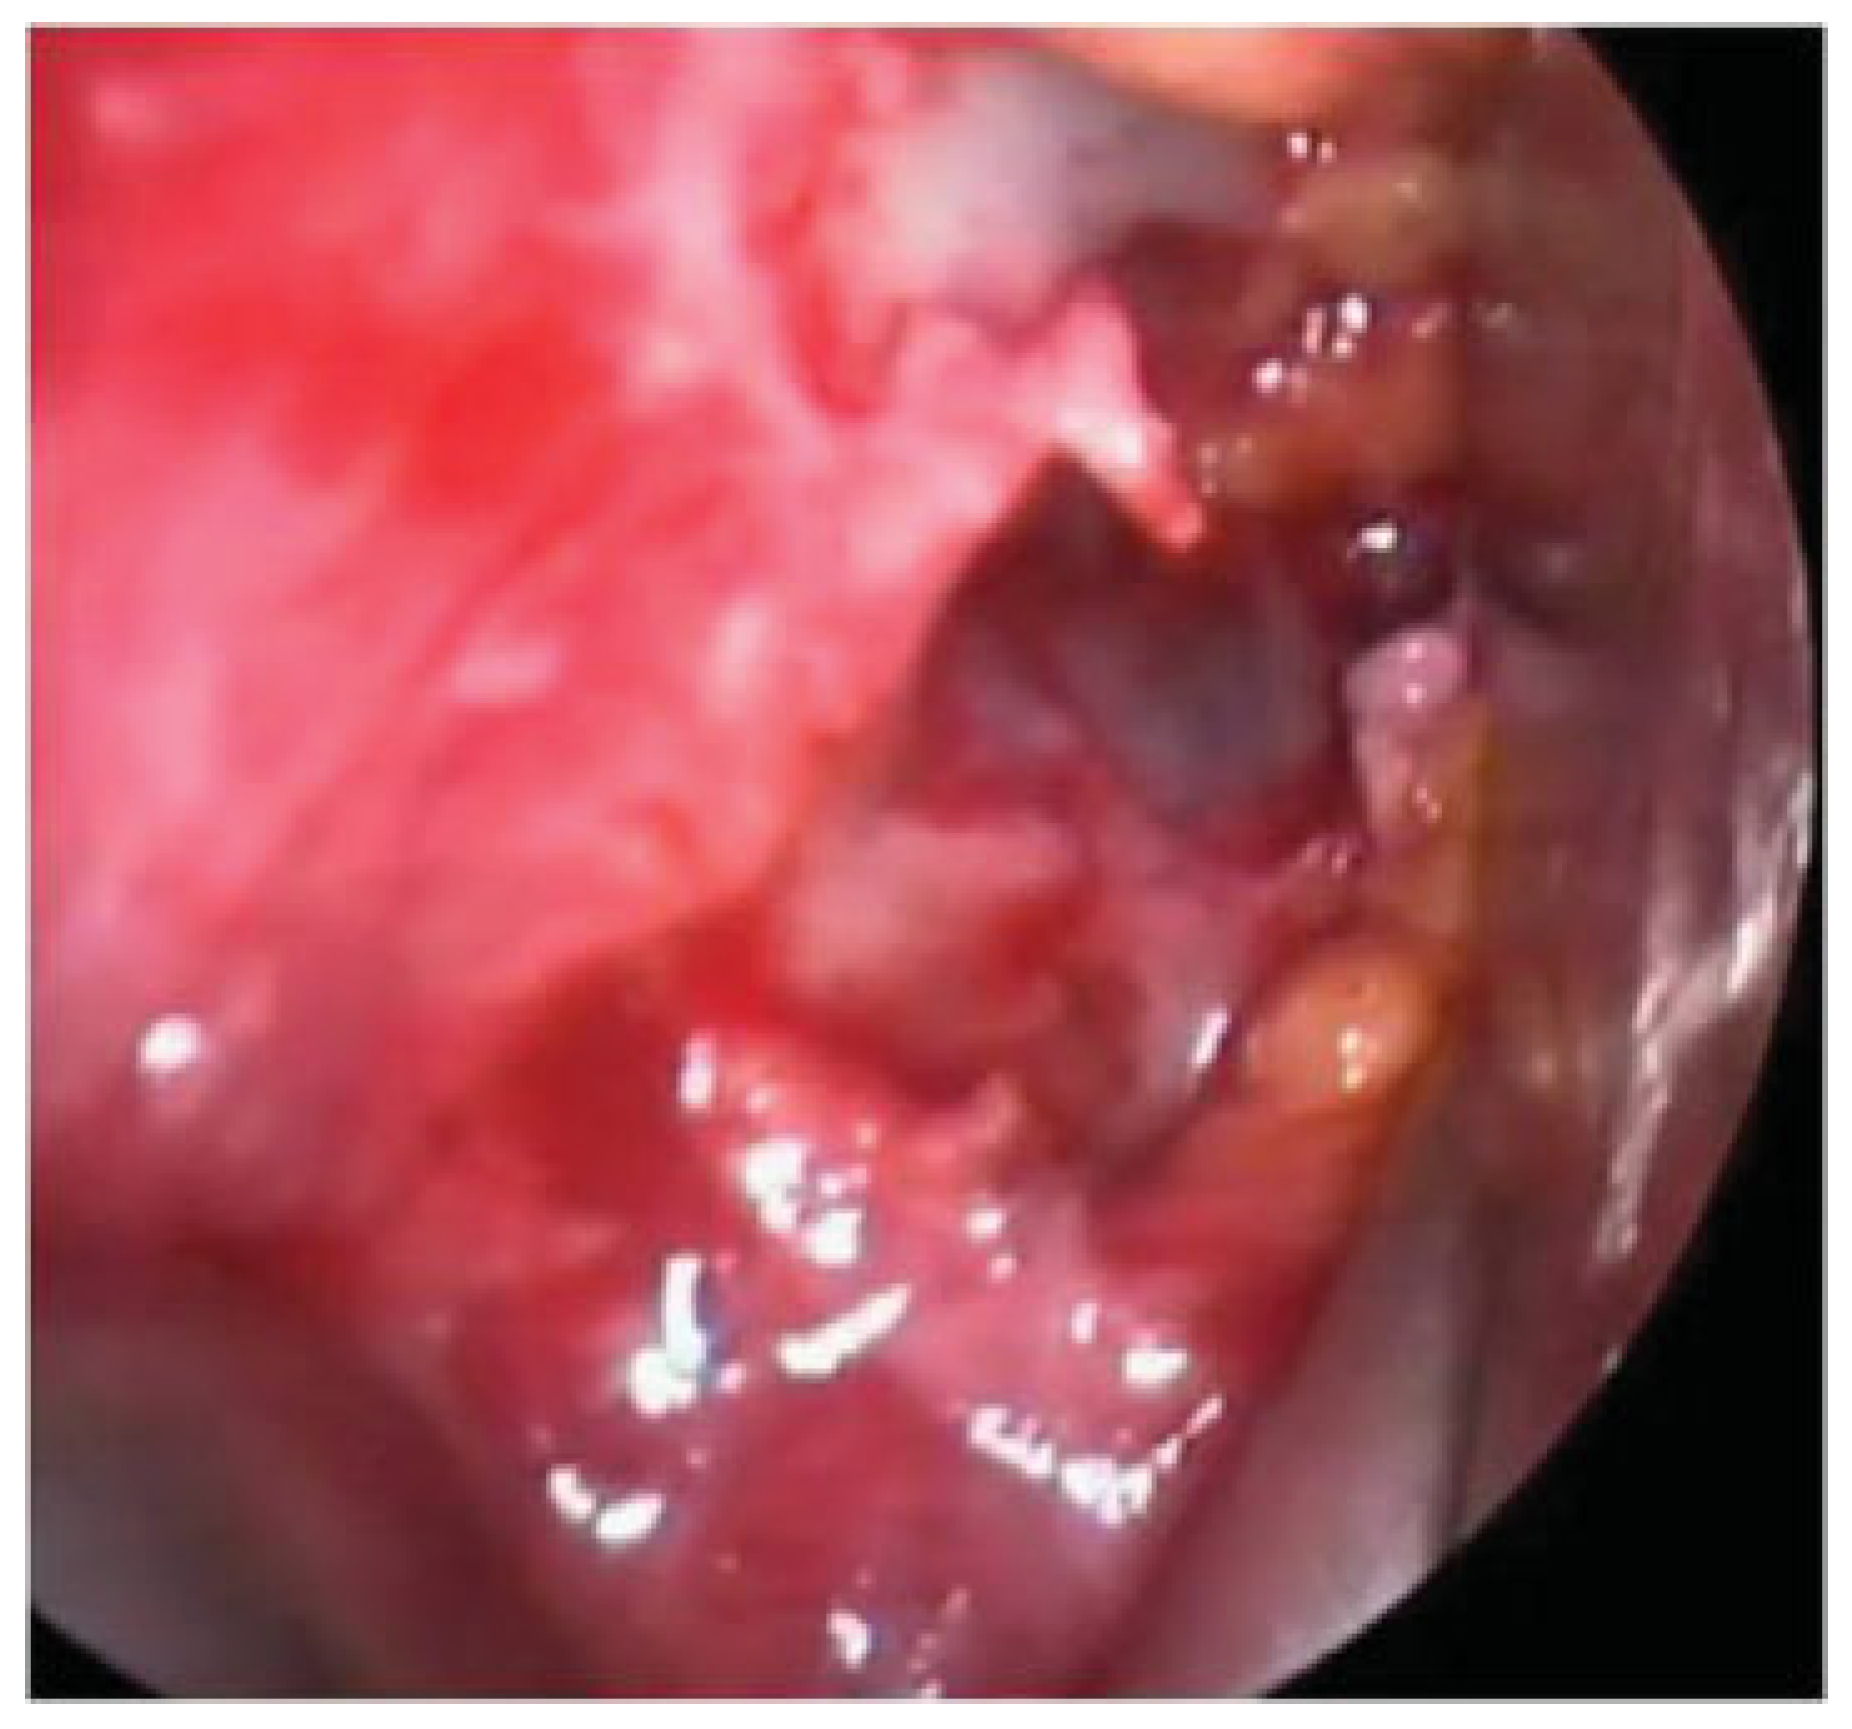

The outcomes measures are summarized in Table 3. The quality of orbital reconstruction was assessed as satisfactory in 12 cases, good in 4 cases, Unsatisfactory in 2 cases. In particular in group 1 (CONV) in four of eight patients, the posterior ledge of the fracture was not reached by the implant (Figure 1a), and in one patients in group 1 the mesh hinged toward the ethmoid (Figure 1b). In group 3 (NAVI) in one of five patients, the posterior ledge of the fracture was not reached.

In our case series, in group 1 (CONV), 4 of 10 implants did not reach the posterior ledge, whereas 1 prebent implant had a wrong angulation hinging toward the ethmoid.

Figure 1. Group 1 (CONV). CTscan images of patients with unsatisfactory orbital reconstruction: (a) titanium mesh not reaching the posterior ledge of a medial wall fracture. The orientation is correct (b) titanium mesh hinged toward the ethmoid.